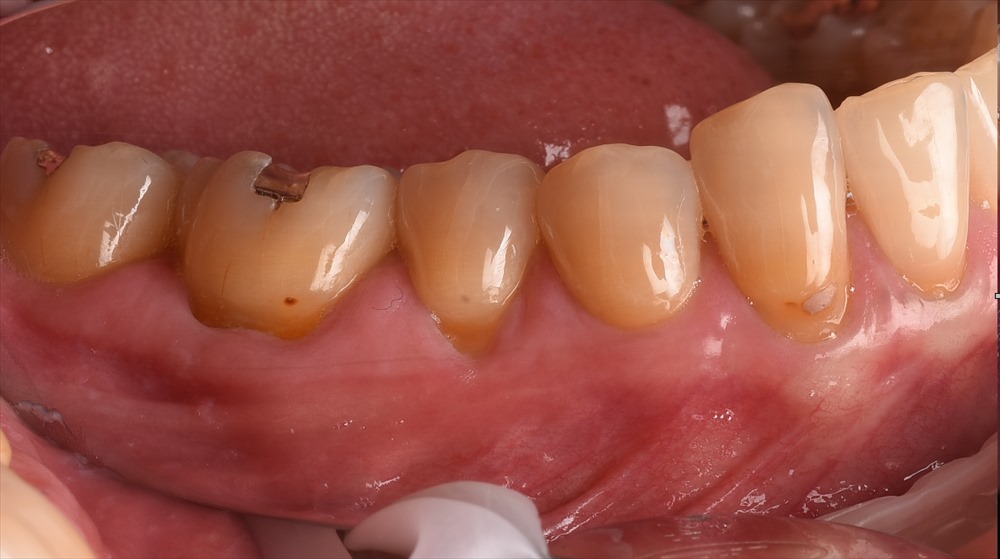

本日は歯茎下がりでお悩みの患者さま。左下がしみて我慢できなくなって当専門医へ受診された症例です。

左下の5番6番の歯茎が下がり、しみて食事がつらい状態でした。